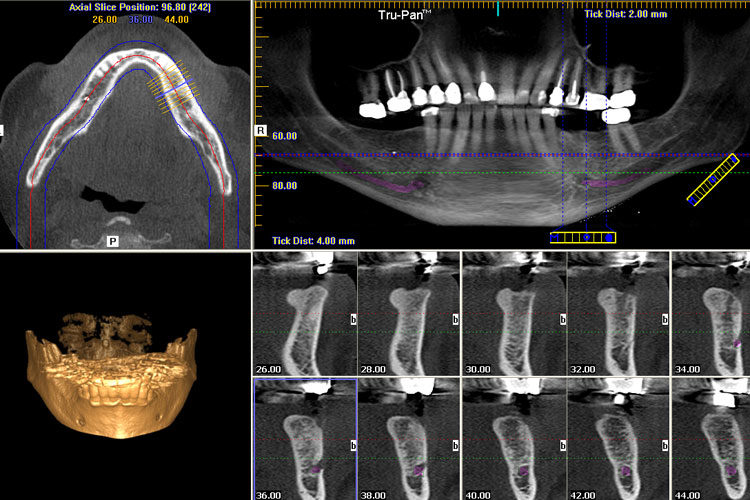

Technical Deep Dive: CBCT Imaging Systems – Engineering Principles & Clinical Impact

2. AI-Driven Reconstruction: Beyond FDK Algorithms

Clinical Accuracy Improvements: Quantified Metrics

Quantitative Analysis Pipelines

Onboard analytics compute:

- Bone quality index (BQI) via HU histogram analysis (R2=0.89 vs. histomorphometry)

- Nerve canal deviation probability using Monte Carlo simulation of drill paths

- Automated pathology detection (sensitivity: 94.2% for cysts >3mm)